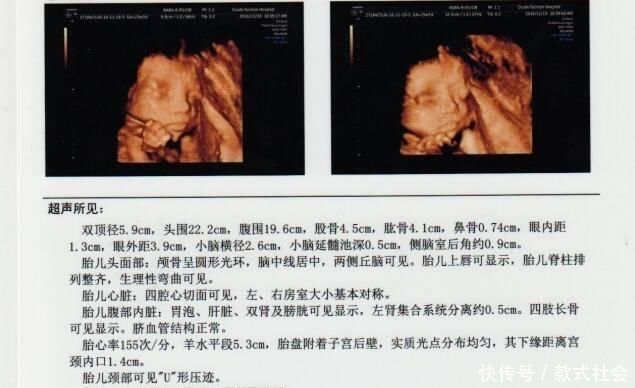

其实对孕妈来说,检查报告最不明确的应该是各个数据的意义,比如图示的双顶径5.9cm,这个双顶径是什么?5.9cm标准吗?对胎儿有哪些影响呢?所以说,只要明确了几个重要数据的意义,那检查报告对孕妈来说,看起来就会很容易了。

如图示,羊水平段5.3cm。这个羊水平段,也就是羊水深度,是指B超检查的最大羊水池的垂直深度,正常范围为3-8cm,小于3cm羊水过少,大于8cm羊水过多,过多多少都得重视。

胎心率也是每次B超检查必须的,对胎儿来说非常重要,胎心率正常值为120-160次/分钟,如果低于120次/分钟,或者高于160次/分钟,都代表胎儿宫内异常,可能有缺氧危险。